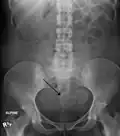

-

A very large (9 cm) fibroid of the uterus which is causing pelvic congestion syndrome as seen on CT -

Two calcified fibroids (in the uterus)